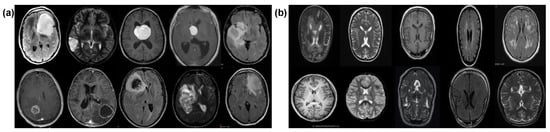

3.1. Dataset Description